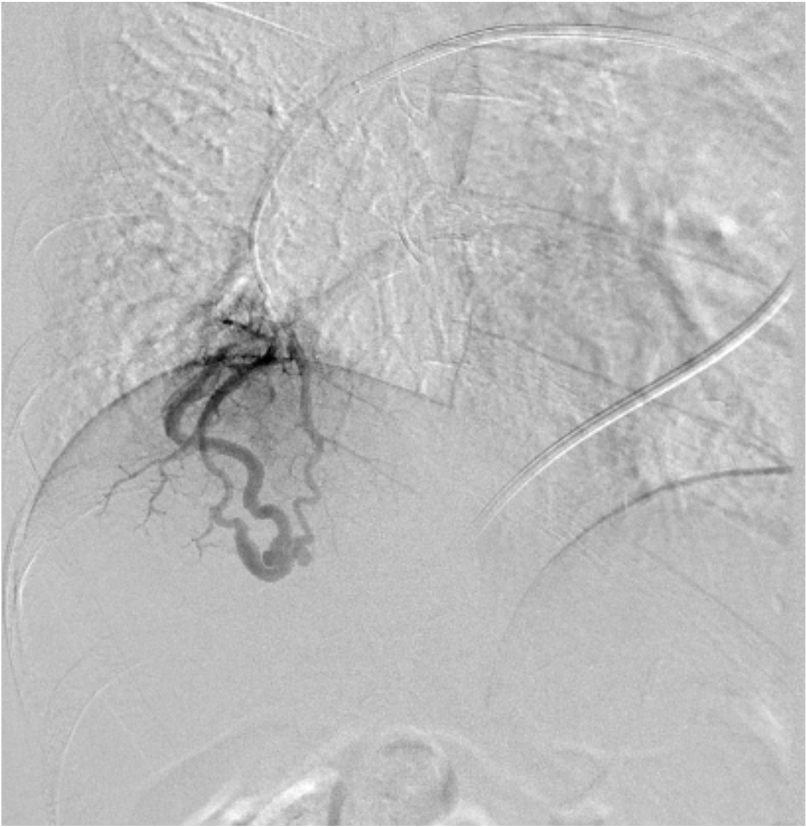

尿路の精査目的で施行した単純CTで, 偶発的に右肺下葉に肺動静脈奇形を認めた. 症状はなく, 流入動脈径は細径であったが, 今後, 脳梗塞などの神経学的合併症を引き起こす可能性があることから, 血管塞栓術の方針となった. 治療方針決定のため, 造影CTを施行した. 造影CTを参照して血管造影, コイル塞栓術を施行し, 良好な治療効果が得られた.

肺動静脈奇形(肺動静脈瘻)の塞栓術の重要性は近年高くなっており, 術前造影CTでの解剖学的評価, 治療戦略が重要である. 従来は3mm以上の流入動脈をもつ肺動静脈奇形が塞栓術の適応とされていたが, 3mm以下の小さな流入動脈をもつ肺動静脈奇形でも重篤な脳神経合併症を起こすことがあり, 現在は流入動脈のサイズに関わらず治療適応と考えられている1-2).

肺動脈は体動脈よりも壁のコンプライアンスが高いため伸縮しやすく, また肺動脈内では線溶系が亢進しているため血栓が溶解されやすい状態とされる. そのため肺動静脈奇形では塞栓術後の再発率が高いことが報告されており, 再発を予防するためには適切なコイルサイズ, 十分な量のコイルを使用するtight packingが必要である. 肺動静脈奇形では複数の流入動脈を有するものも少なくなく, 術前CTにて流入動脈の解剖を十分検討することが重要である.